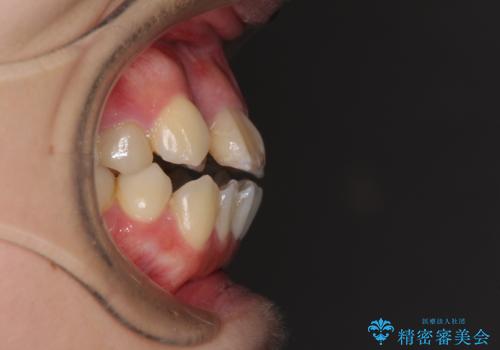

- 八重歯と前歯のデコボコ、開咬を気にして来院された患者様です。

抜歯矯正が必要であることはご自身で理解されており、目立たない装置をご希望であったので、上顎が裏側装置であるハーフリンガル装置にて治療を行うこととしました。